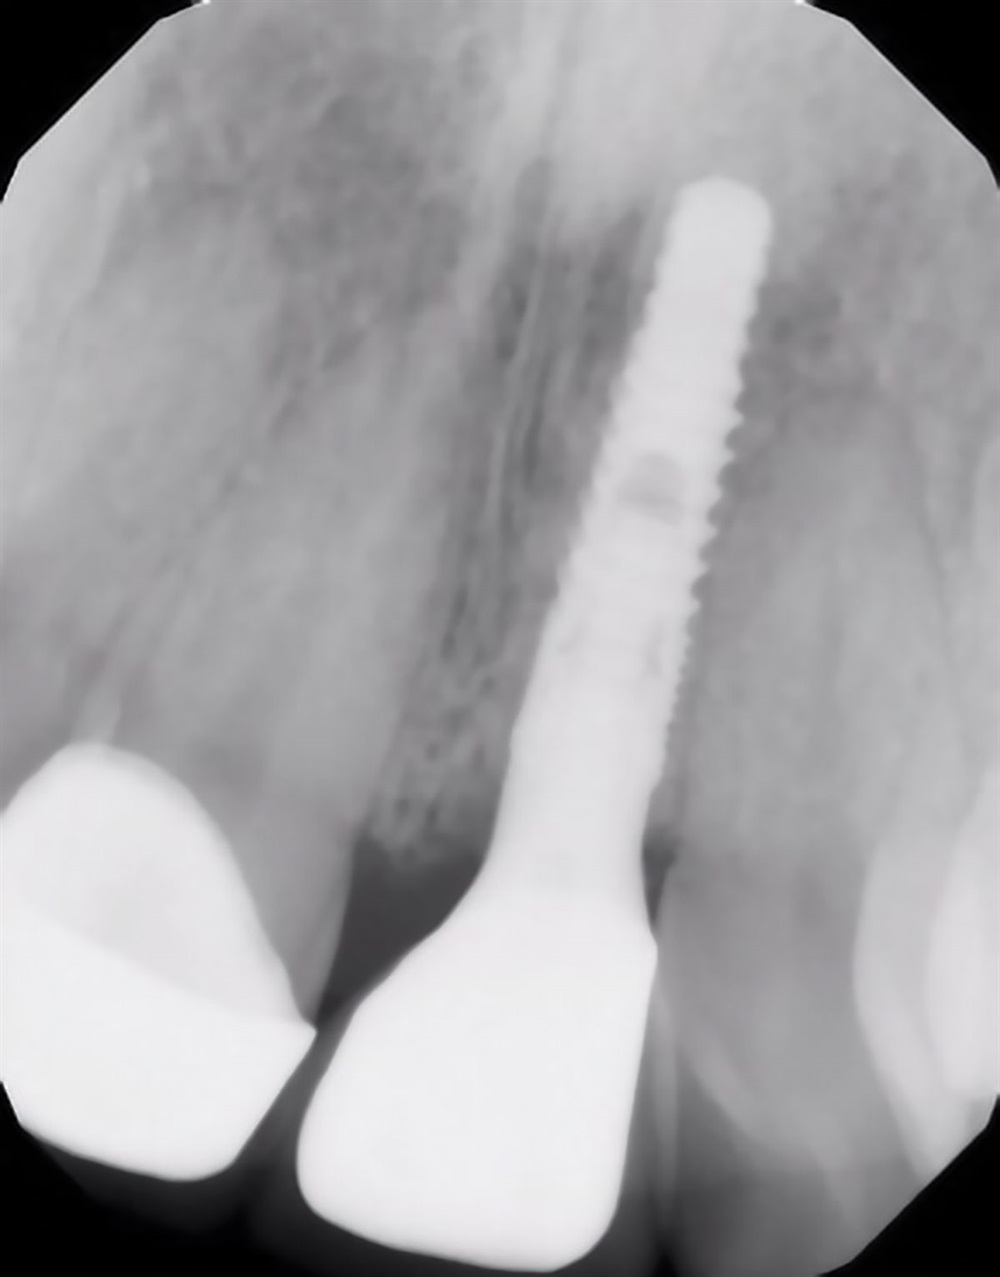

Dentis implants. An implant with a tapered design, platform switching, and it’s available as both resorbable blast media (RBM) and sandblasted, large-grit, acid-etched (SLA) surface treatments. I find the surgical and prosthetic armamentarium very straightforward, and the built-in drill stops for each available length provide a strong safety margin. Also, both the healing and prosthetic abutments are designed with a concave emergence, which allows for thicker soft-tissue and subcrestal placement of the implants without impinging on the gingiva and bone.

This remains one of my favorite cases because it really displays the success one can have with anterior implant cases. I was using a modified “dual zone therapy” technique (developed by Drs. D.P. Tarnow and S.J. Chu), which I have found to have great utility in an office where making immediate provisionals does not fit the workflow.